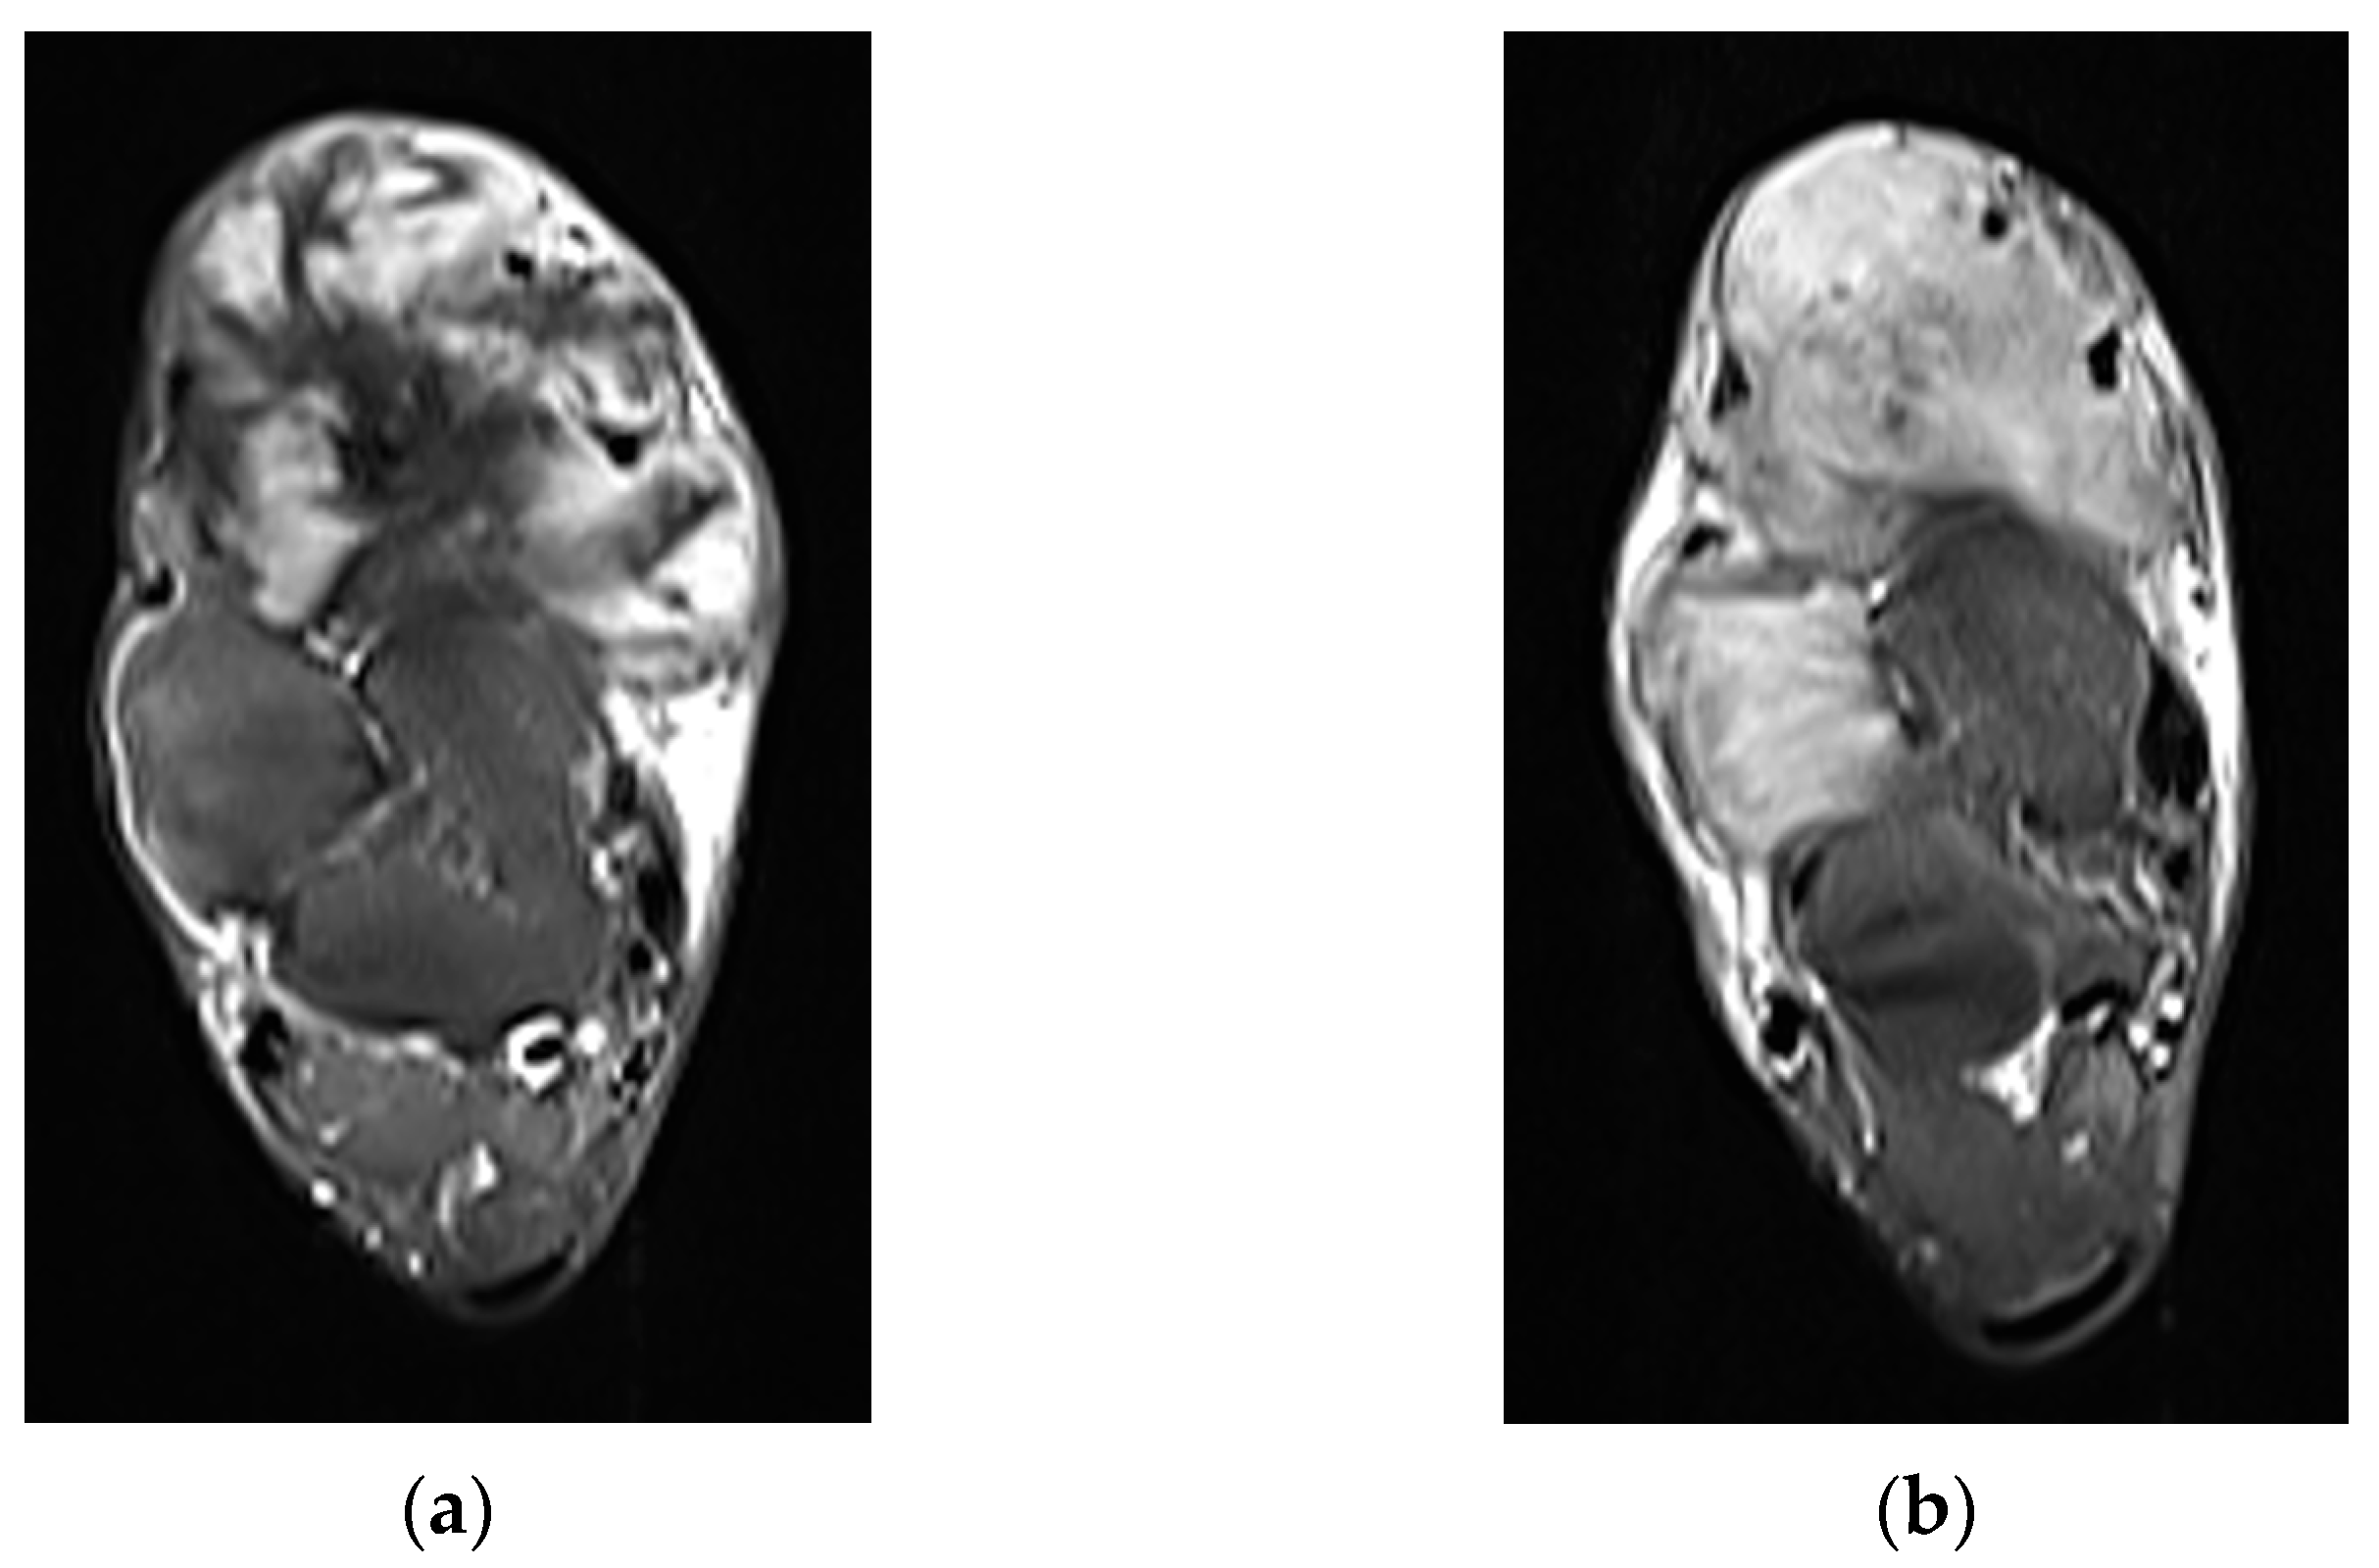

| MRI | Well-circumscribed, heterogenous with nonenhancing T1/T2 hypointense curvilinear areas related to collagen, and T1 intermediate to low/T2 intermediate to high areas related to cellularity or the myxoid matrix. Additional secondary signs (“flame”, “staghorn”, “fascial tail”, etc.) are described in text. |